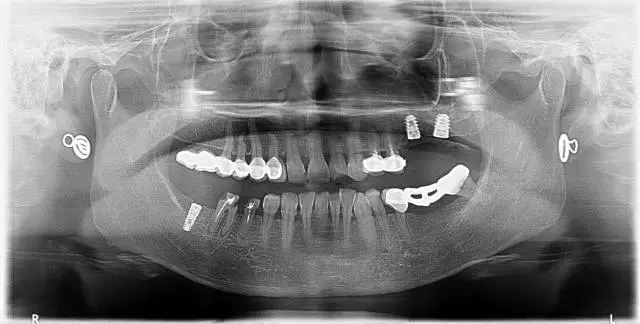

4、 全景片

2、治療后

6、26,27,47種植修復(fù)(2014年1月)